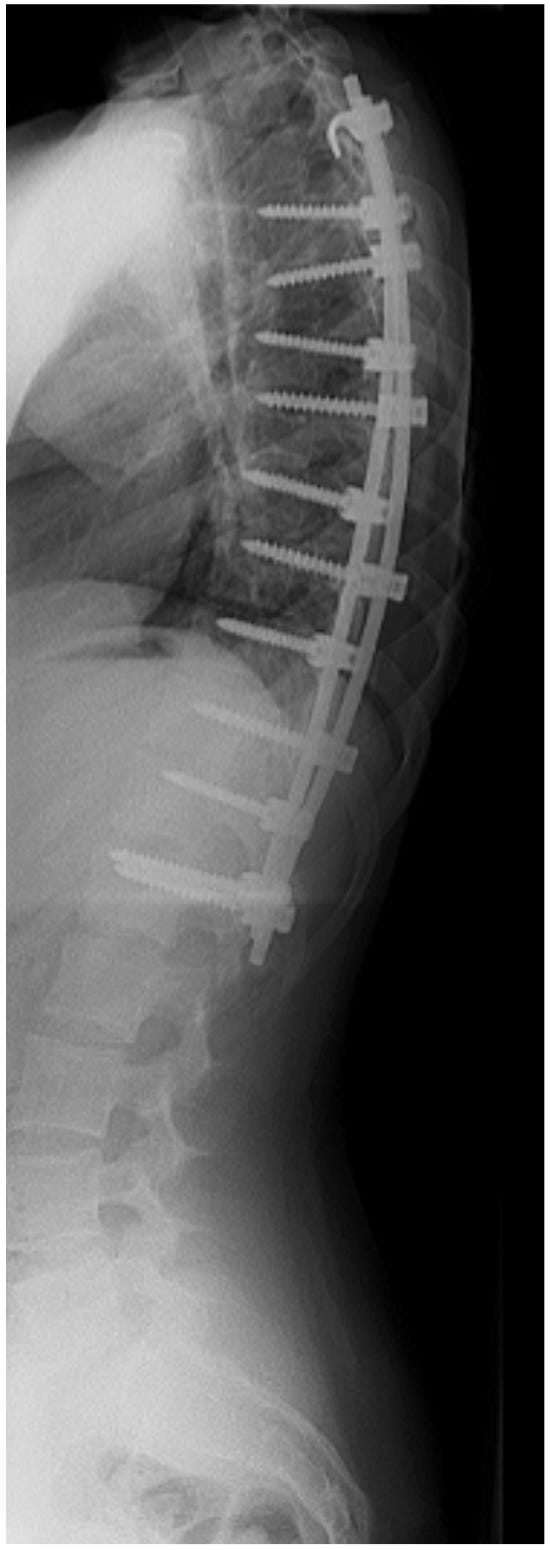

De wervelkolom wordt vastgezet met behulp van metalen staven en schroeven. Op sommige plaatsen maakt de chirurg de wervels beter passend door wat bot weg te halen. Dit zorgt ervoor dat alles stevig vast groeit.

Op de röntgenfoto’s kun je zien hoe de wervelkolom er voor en na de operatie uit ziet.

Figuur 1: scoliose voor de operatie

Figuur 2: scoliose na de operatie